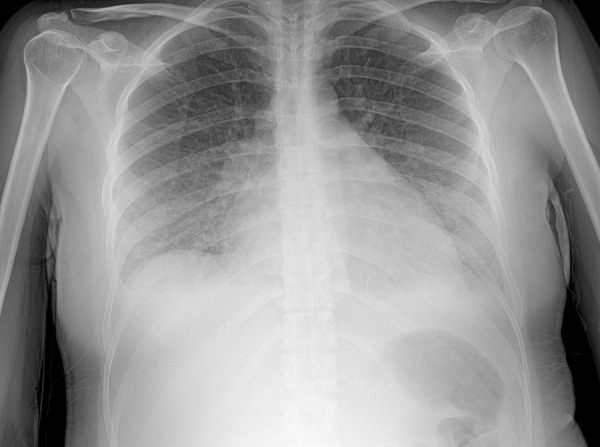

Peripartum cardiomyopathy (PPCM) is a potentially life-threatening condition that can occur during the late pregnancy or puerperium. A 31-year-old woman with a recent twin pregnancy presented with heart failure symptoms nine days postpartum. On admission, she had volume overload and hemodynamic compromise, which was rapidly reversed with inotropic levosimendan support. Echocardiography revealed a left ventricular ejection fraction (LVEF) of 20% with global hypokinesia. Once stabilized, she was discharged on heart failure medication, bromocriptine, and warfarin. Cardiac magnetic resonance imaging at five weeks demonstrated a preserved LVEF of 57% and no evidence of myocardial scarring or edema. During the 4-year follow-up, the patient remained stable with no new pregnancies. This case highlights the importance of considering PPCM in the differential diagnosis of heart failure in the peripartum period after excluding other etiologies. It also describes the successful use of bromocriptine in facilitating recovery of systolic function without long-term complications.